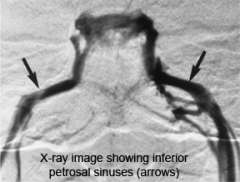

Inferior petrosal sinus sampling

In some cases, MRI fails to identify an abnormality. If your doctor suspects Cushing's disease, he or she may order super-selective inferior petrosal sinus sampling (IPSS).

IPSS must be performed by an experienced interventional neuroradiologist because it carries risk, and if done inappropriately, can give misleading results.

The inferior petrosal sinuses are veins that occur on both sides of the pituitary gland.

- Blood leaving the right half of the pituitary gland drains into the right inferior petrosal sinus and vice versa.

- Specially trained interventional neuroradiologists can thread a tiny catheter into the inferior petrosal sinus. Blood samples are then taken from each sinus and from a vein just below the heart.

If the ACTH level is the same in the inferior petrosal sinus compared to the vein below the heart, this suggests that a tumor somewhere else in the body (ectopic, not pituitary) is producing ACTH.

In Cushing's disease, the ACTH level in the inferior petrosal sinus is much higher compared to the vein below the heart